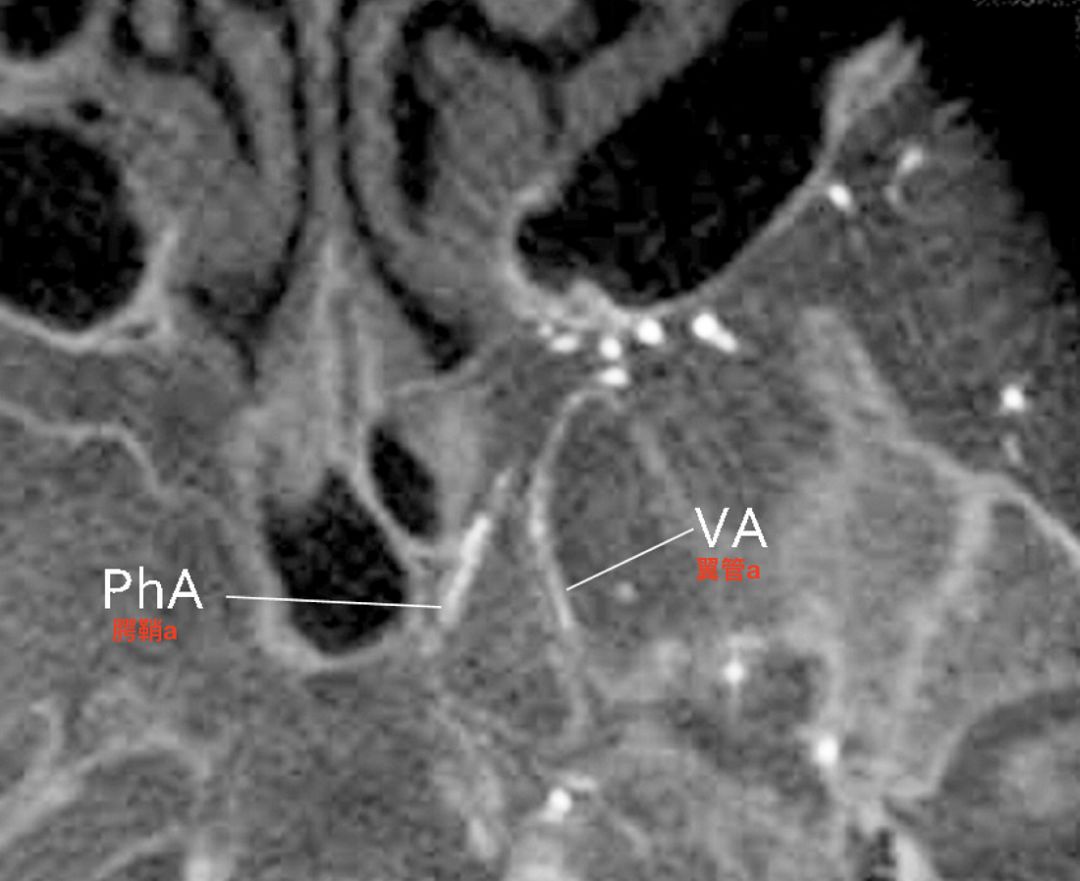

翼管动脉发自颈内动脉岩段的水平段,在翼管内与翼管神经伴行。翼管动脉在翼腭窝内与上颌内动脉吻合(Osawa 2009)。

颈内动脉近端闭塞病人,左侧颈外动脉CTA水平位重建(Tanoue 2013)。显示翼管动脉向后走行进入翼管。